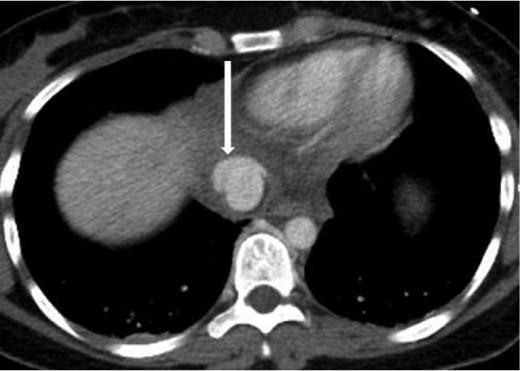

Axial contrast-enhanced CT of the chest showing abnormal contour of the supradiaphragmatic IVC with ventrally and laterally confined contrast extravasation (arrow) consistent with a pseudoaneurysm surrounded by pericaval hematoma.

Axial contrast-enhanced CT of the abdomen performed 30 min after the initial CT of the chest showing persistence of the abnormal contour of the supradiaphragmatic IVC with contrast extravasation confined laterally and ventrally (arrow), nonexpanding pericaval hematoma.